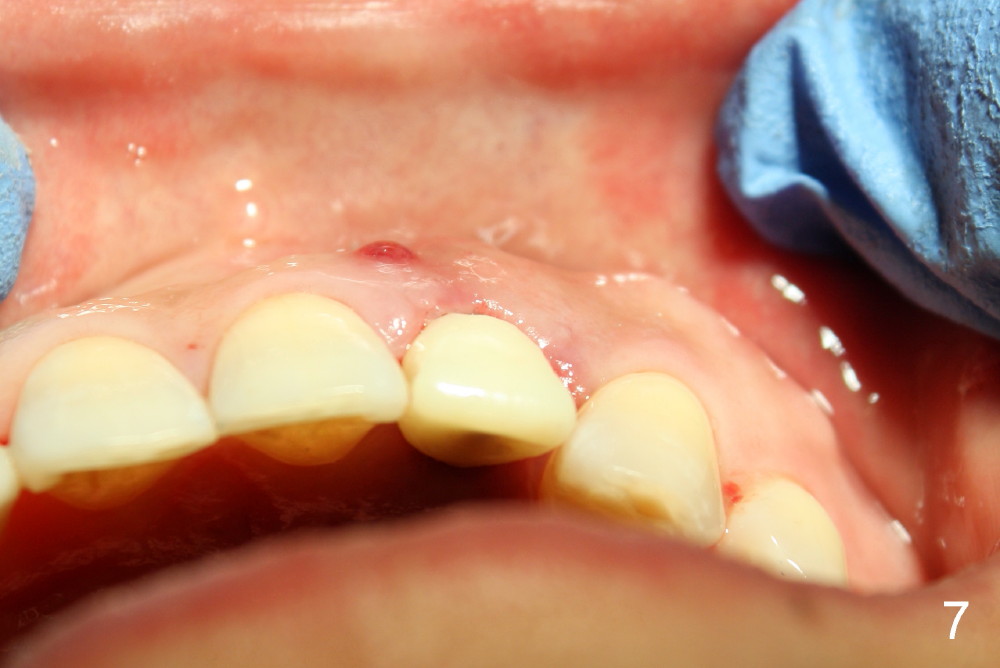

Within one week, the infection resolves (Fig.8,9).

The gingival architecture around the immediate provisional is normal 5 months postop (Fig.10,12). To increase cosmetics for the definitive restoration, the abutment length is reduced (compare arrowheads in Fig.11 to 12).